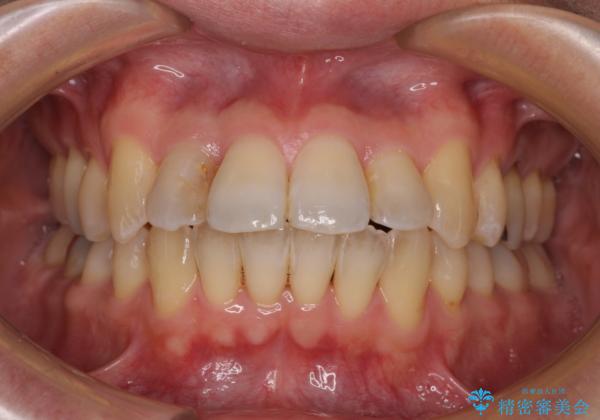

前歯のクロスバイト 目立たないワイヤー装置で矯正治療

- 前歯のクロスバイトを改善したいとのことで来院された患者様です。

舌の突出癖の影響か、下顎前歯がなかなか整わず、治療期間は予定よりも長期間となりました。